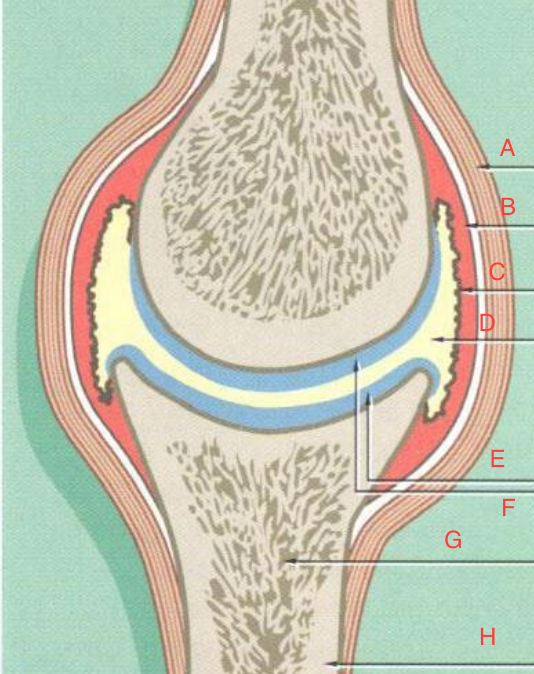

A) Ligament B) Joint capsule C) Synovial lining D) Synovial cavity E/F) Articular cartilage G) Medullary trabecular bone H) Cortical Bone